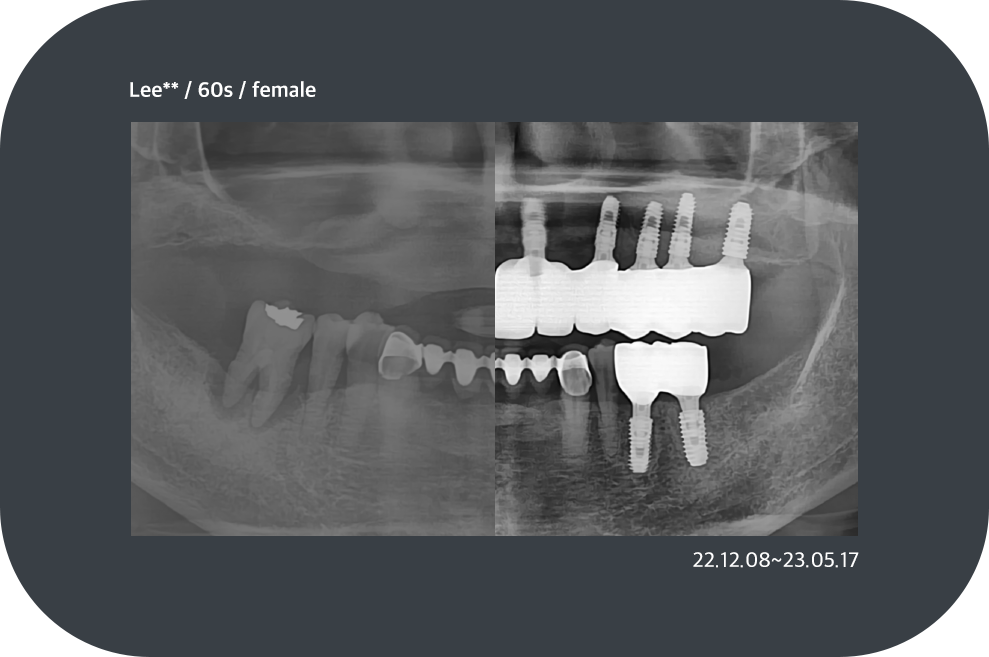

치료사례

임플란트 치료사례

implant_case01

implant_case02

implant_case03

implant_case04

*모든 증례 사진은 의료법 제23조, 제56조에 의거하여, 당사자의 동의하에 게시하였습니다.

*치료 사진은 모두 본원에서 치료한 환자분의 사진입니다.

*치료 사진은 모두 동일인의 사진이며, 동일조건에서 촬영하였습니다.

*개인의 차이에 따라 시술 및 수술 후 부작용이 발생할 수 있으며, 의료진과 충분한 상담을 받으시기 바랍니다.